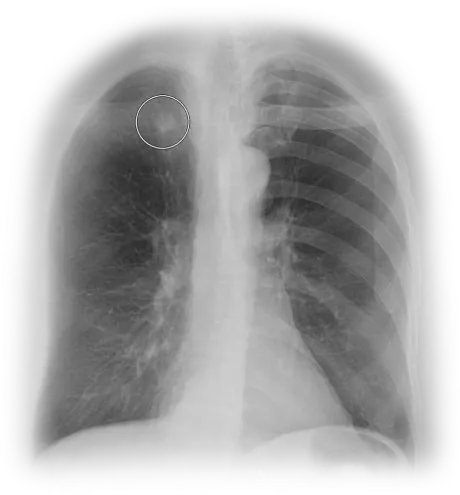

Lung cancer, cardiac disease and emphysema are leading global killers. Earlier detection and treatments of these conditions improves patient outcomes. However, detection is complex and time-consuming. The ClearRead TM cardiothoracic AI suite is purpose-built to improve accuracy and efficiency on chest CTs and X-rays, covering all the bases for a population health approach to the early detection of cardiothoracic conditions.

Our ClearRead Chest imaging interpretation solutions are built upon advanced AI algorithms that target the biggest health threats globally. We accurately and efficiently improve outcomes for improved patient care with tools that target pulmonary nodules, coronary artery calcification (CAC), and pneumothoraces. Learn more about the ClearRead solutions built for lung and cardiac conditions.